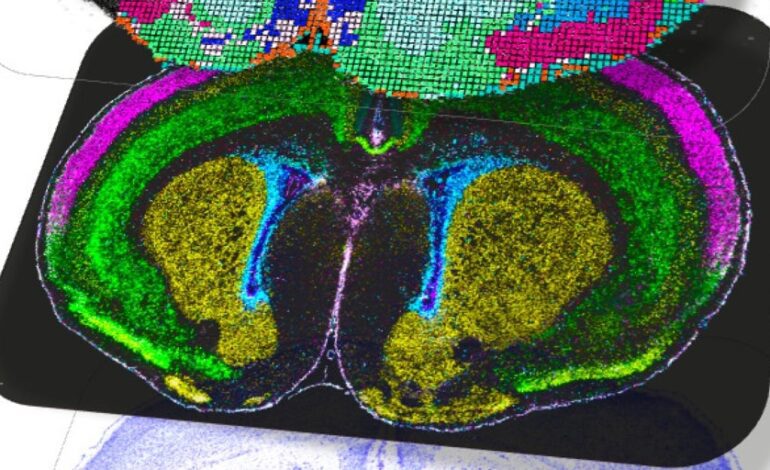

Del autismo al autismo y a la esquizofrenia. Información publicada en ‘Nature’ de 12 estudios del consorcio internacional BRAIN Initiative Cell Atlas Network (BICAN) sobre los mapas más detallados hasta la fecha del desarrollo cerebral en mamíferos, incluidos los ratones, … sino también en humanos, proporciona información detallada sobre cómo nacen y maduran los diferentes tipos de células cerebrales a lo largo del tiempo y, según los autores, estos datos permitirán empezar a descubrir cómo las alteraciones en este proceso pueden conducir a trastornos como el autismo o la esquizofrenia.

Los resultados revelan con una resolución sin precedentes cómo los diferentes tipos de emergen las células cerebrales y especializarse desde las primeras etapas de la vida, así como los factores genéticos y ambientales que influyen en estos procesos

Utilizando tecnologías de secuenciación unicelular y herramientas avanzadas de mapeo espacial, los investigadores pudieron seguir paso a paso cómo las células madre se transforman en neuronas y células gliales, y cómo éstas se organizan en redes funcionales.

Los atlas producidos por BICAN incluyen datos de más de 1,2 millones de células cerebrales y abarcan desde ratones hasta humanos. Estos recursos muestran que el desarrollo neuronal continúa incluso después del nacimiento, particularmente en las regiones involucradas en el aprendizaje, la toma de decisiones y las emociones, lo que sugiere que el cerebro conserva una plasticidad notable durante la infancia.